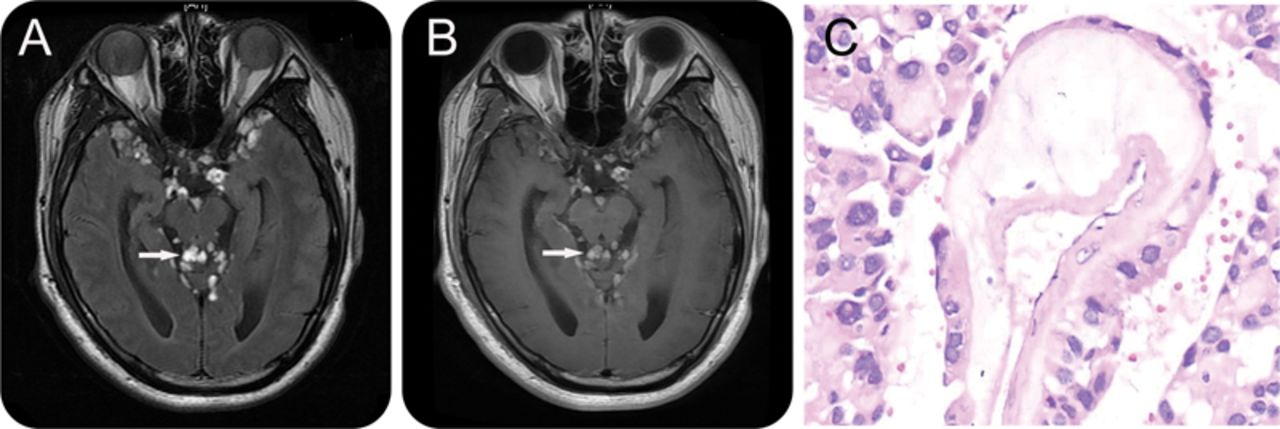

图2

颅核磁共振成像和组织病理学

轴向T2 (A)和t1 (B)大脑的核磁共振显示分散的结节状病灶hyperintense fluid-attenuated反转恢复图像和轻度对比度增强(白色箭头)。显微照片(C)揭示了肿瘤细胞形成乳头状结构。黏液状的肿瘤细胞和血管之间的材料被认为(400×)。